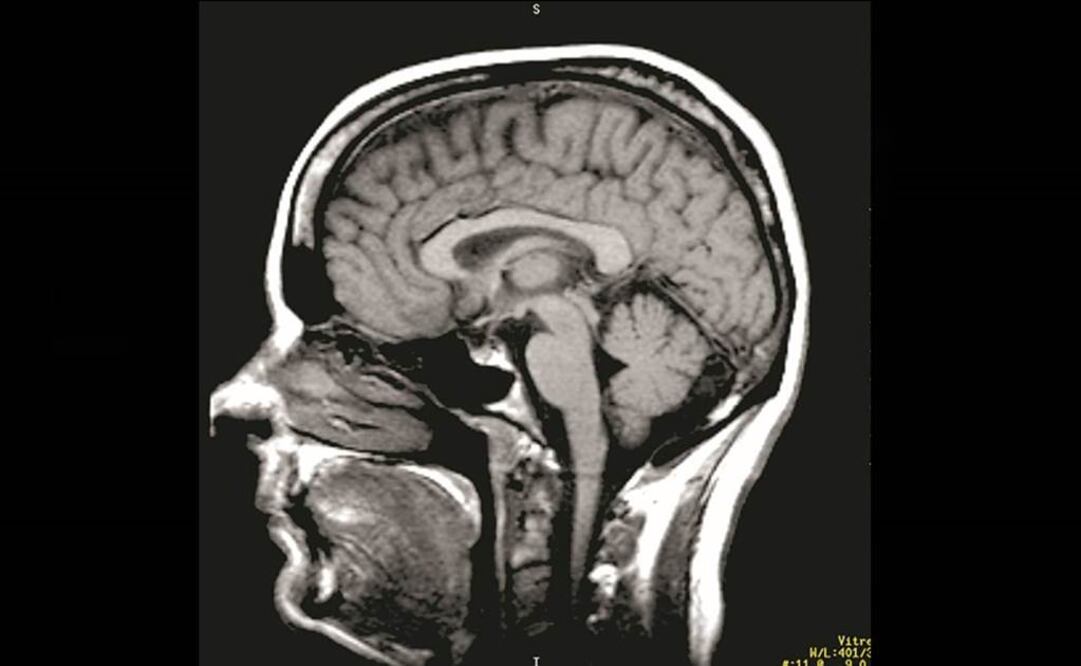

El especialista explicó que el Alzheimer es la forma más común de la demencia, una enfermedad degenerativa del sistema nervioso central, principalmente del cerebro, que produce la perdida de las funciones mentales como la memoria y de otras habilidades intelectuales.